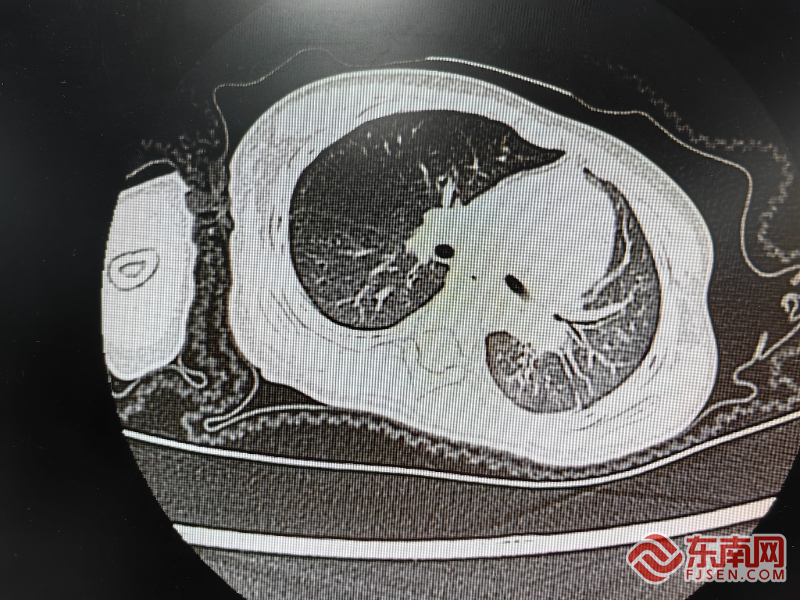

肺部影像。闽东医院供图

东南网宁德1月7日讯(本网记者 周涛 通讯员 钱红姣)近日,福安市1岁11月小欣突发高热,呼吸困难,食欲和精神非常差,焦急万分的家长带其到闽东医院儿科求诊,经过医生仔细检查,发现左侧呼吸音明显减低,肺部影像提示左侧“肺不张”,遂急诊收治入院。

在充分评估病情并征得家长同意后,立即为患儿进行纤维支气管镜检查和肺泡灌洗,洗出了大量的痰液和支气管塑形,患儿症状马上得以缓解,左侧呼吸音基本正常。经抗感染、保持呼吸道通畅等治疗,五天后复查肺部CT,肺部支气管通畅,炎症较前明显吸收,精神食欲好转,儿童“活蹦乱跳”地出院了。